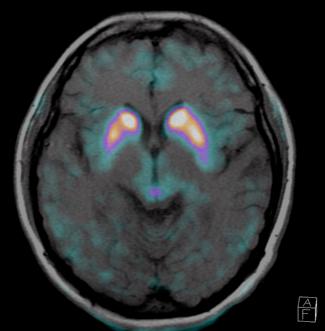

CASO CLÍNICO

Actualmente, el diagnóstico del Parkinson se basa principalmente en métodos convencionales que incluyen: -Presencia de 2 de los 3 síntomas principales, con ausencia

axial fusionada de PET-RM 3T con

con disminución de la captación del radiotrazador a nivel de ambos putámenes en la región posterior y media de predominio derecho así como disminución en el caudado ipsilateral.

2. Reconstrucción tridimensional avanzada de imagen híbrida PET-RM 3T con 6-[18F]FDOPA observando disminución de la captación del radiotrazador a nivel de ambos putámenes en la región posterior y media así como en el núcleo caudado derecho.

Figura 1. Imagen

6-[18F]FDOPA

Figura

Figura 3. Reconstrucción mediante imagen molecular de imagen híbrida PET-RM 3T con 6-[18F] FDOPA observando disminución de la captación del radiotrazador a nivel de ambos putámenes en la región posterior, media y anterior así como en ambos núcleos ca dados de predominio derecho.

Figura 4. Reconstrucción mediante imagen molecular de imagen híbrida PET-RM 3T con 6-[18F]FDOPA observando captación adecuada y conservada del radiotrazador en el cuerpo estriado (ambos putámenes y núcleos caudados) en un paciente negativo para enfermedad de parkinson.

En cuanto al campo de los estudios de imagen convencional y de laboratorio no existe alguna prueba que pueda confirmar la enfermedad. Sin embargo, las imágenes de diagnóstico por métodos de imagen molecular del tipo no invasivas, como la tomografía por emisión de positrones (PET) en conjunto con un resonador de 3 tesla (RM 3T), pueden respaldar el diagnóstico de un médico, actualmente éste método tiene una sensibilidad diagnóstica de 95.4%, especificidad 100%, valor predictivo positivo del 100% y valor predictivo negativo del 87.5%. (5,6)

La enfermedad de parkinson es una enfermedad neurodegenerativa con afectación principalmente motora (temblor, rigidez y acinesia) de sospecha y diagnóstico clínico, ante la limitación de los estudios de laboratorio y métodos de imagen convencional para el diagnóstico toman gran relevancia las técnicas de imagen molecular no invasivas como el PET-RM y PET-CT con 6-[18F]FDOPA que cuentan con gran sensibilidad y especificidad para respaldar o descartar el diagnóstico médico ante la sospecha de la enfermedad de parkinson y algunas otras enfermedades del trastorno del movimiento.